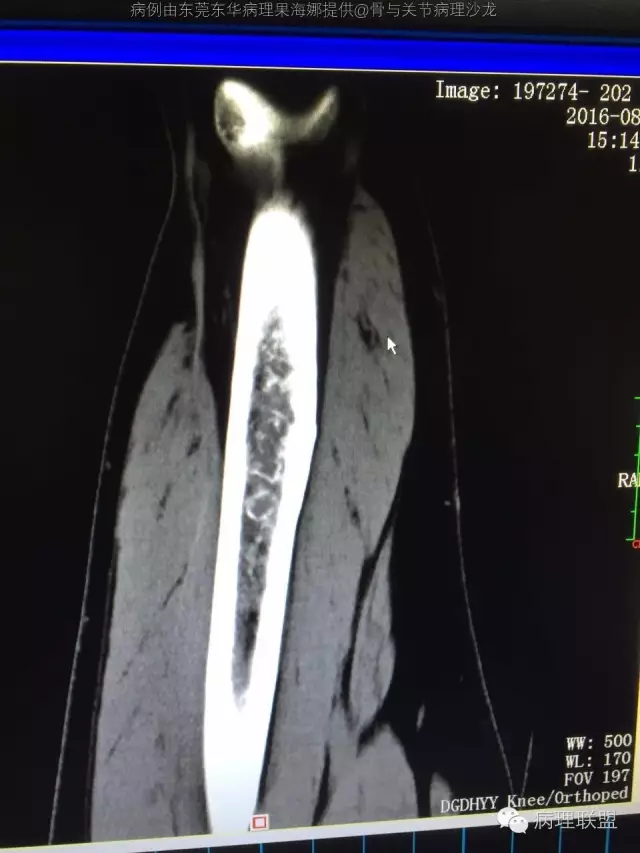

F/35--长骨软骨肉瘤?

F/35(病例由东莞东华医院病理科 果海娜提供,致谢!)

@东莞东华病理果海娜 ,组织学异型不明显,灶性粘液变,骨包软骨,但影像第二张显示可疑皮质侵犯,肿瘤体积较大,故考虑不典型软骨性肿瘤/软骨肉瘤I级

病变长轴与直径比例约4:1恐不善良。

@301病理 王昀 ,请我院影像科骨肿瘤专科教授看了,影像倾向高分化软骨肉瘤

@中山大学附一院病理李扬 我看不太好皮质侵犯,就觉得长轴太长了

长骨的软骨性肿瘤长度大于5cm至少诊断软骨肉瘤1级